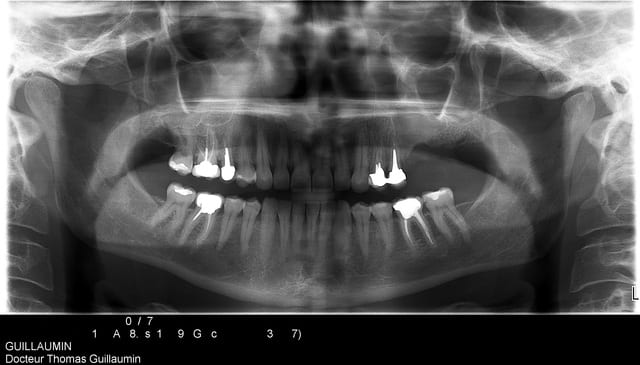

d'abord, je ne te conseille pas de faire ton sinus par voie latérale mais d'utiliser la cbs comme fenêtre d’accès.

voici juste pour commencer la présentation du cas..

50 ans, fumeuse, belle femme, CBS suite à une malheureuse extraction

fermeture de la cbs par un chir maxillo-faciale à l'aide de la boule de Bichat

6 ans plus tard elle se plaint de gênes à ce niveau.

elle veut des dents.

Karine panoramic1 qukyq7 - Eugenol